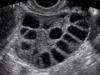

Vad kallas de folliklar som finns hos prepubertal?

Primordialfolliklar